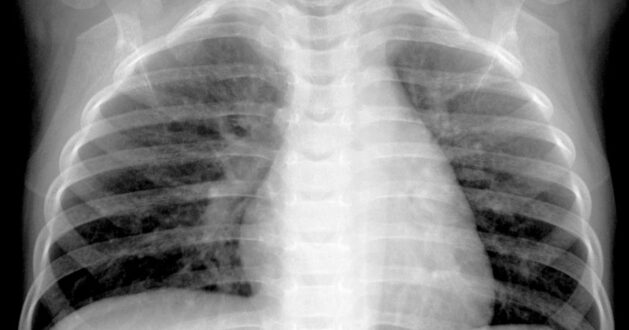

Son zamanlarda hastanelerin aşırı yüklendiği iddialarıyla birlikte dikkatler Çin’deki hMPV vakalarına çekilmiştir. hMPV, kıştan ilkbahara kadar birçok ülkede dolaşan yaygın bir solunum yolu virusudur; ancak hMPV’deki eğilimlere ilişkin veriler tüm ülkeler tarafından rutin olarak yayımlanmaz. Bazı olgular bronşit veya zatürre nedeniyle hastaneye kaldırılabilse de, hMPV ile infekte olmuş çoğu kişide soğuk algınlığına benzer hafif üst solunum yolu semptomları görülür ve birkaç gün sonra iyileşir.